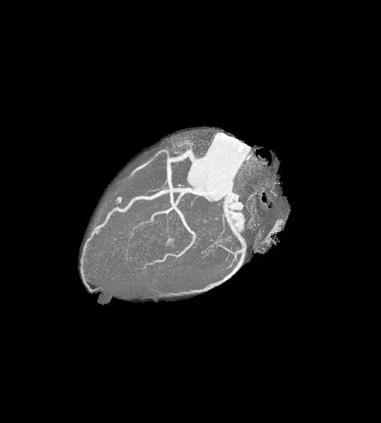

This image from an iCT scanner was done to evaluate coronary artery disease. The scan parameters were: 100 kVp, 50 mAs, CTDI vol 6.3 mGy, DLP 68.3 mGy x cm, iDose4 level = 3, effective dose 0.9 mSv. More images are below.

Southern Ohio Medical Center (SOMC) is a 222-bed, rural, nonprofit hospital in Portsmouth, Ohio, that serves approximately 120,000 patients in the Appalachian area. The computed tomography (CT) department is a 24/7 operation. It has two Philips iCT scanners: one in the emergency department and the other in the medical imaging department, and it utilizes the iDose4 iterative reconstruction technique on iCT scans. Modifying imaging protocols for high image quality while achieving doses as low as reasonably achievable (ALARA) has become an endeavor of the imaging department at SOMC.

Because iDose4 significantly improves spatial resolution and preserves the “natural” appearance of images, image quality improvements are achieved.

“We experimented with low-dose/low-energy scans in the past with suboptimal image quality. Therefore, the dose vs. image quality was not beneficial,” Dean Blair RT(R)(CT), supervisor of the CT department at SOMC said. “Then we installed the iCT with iDose4. Now, our results show an increase in image quality at low dose.”